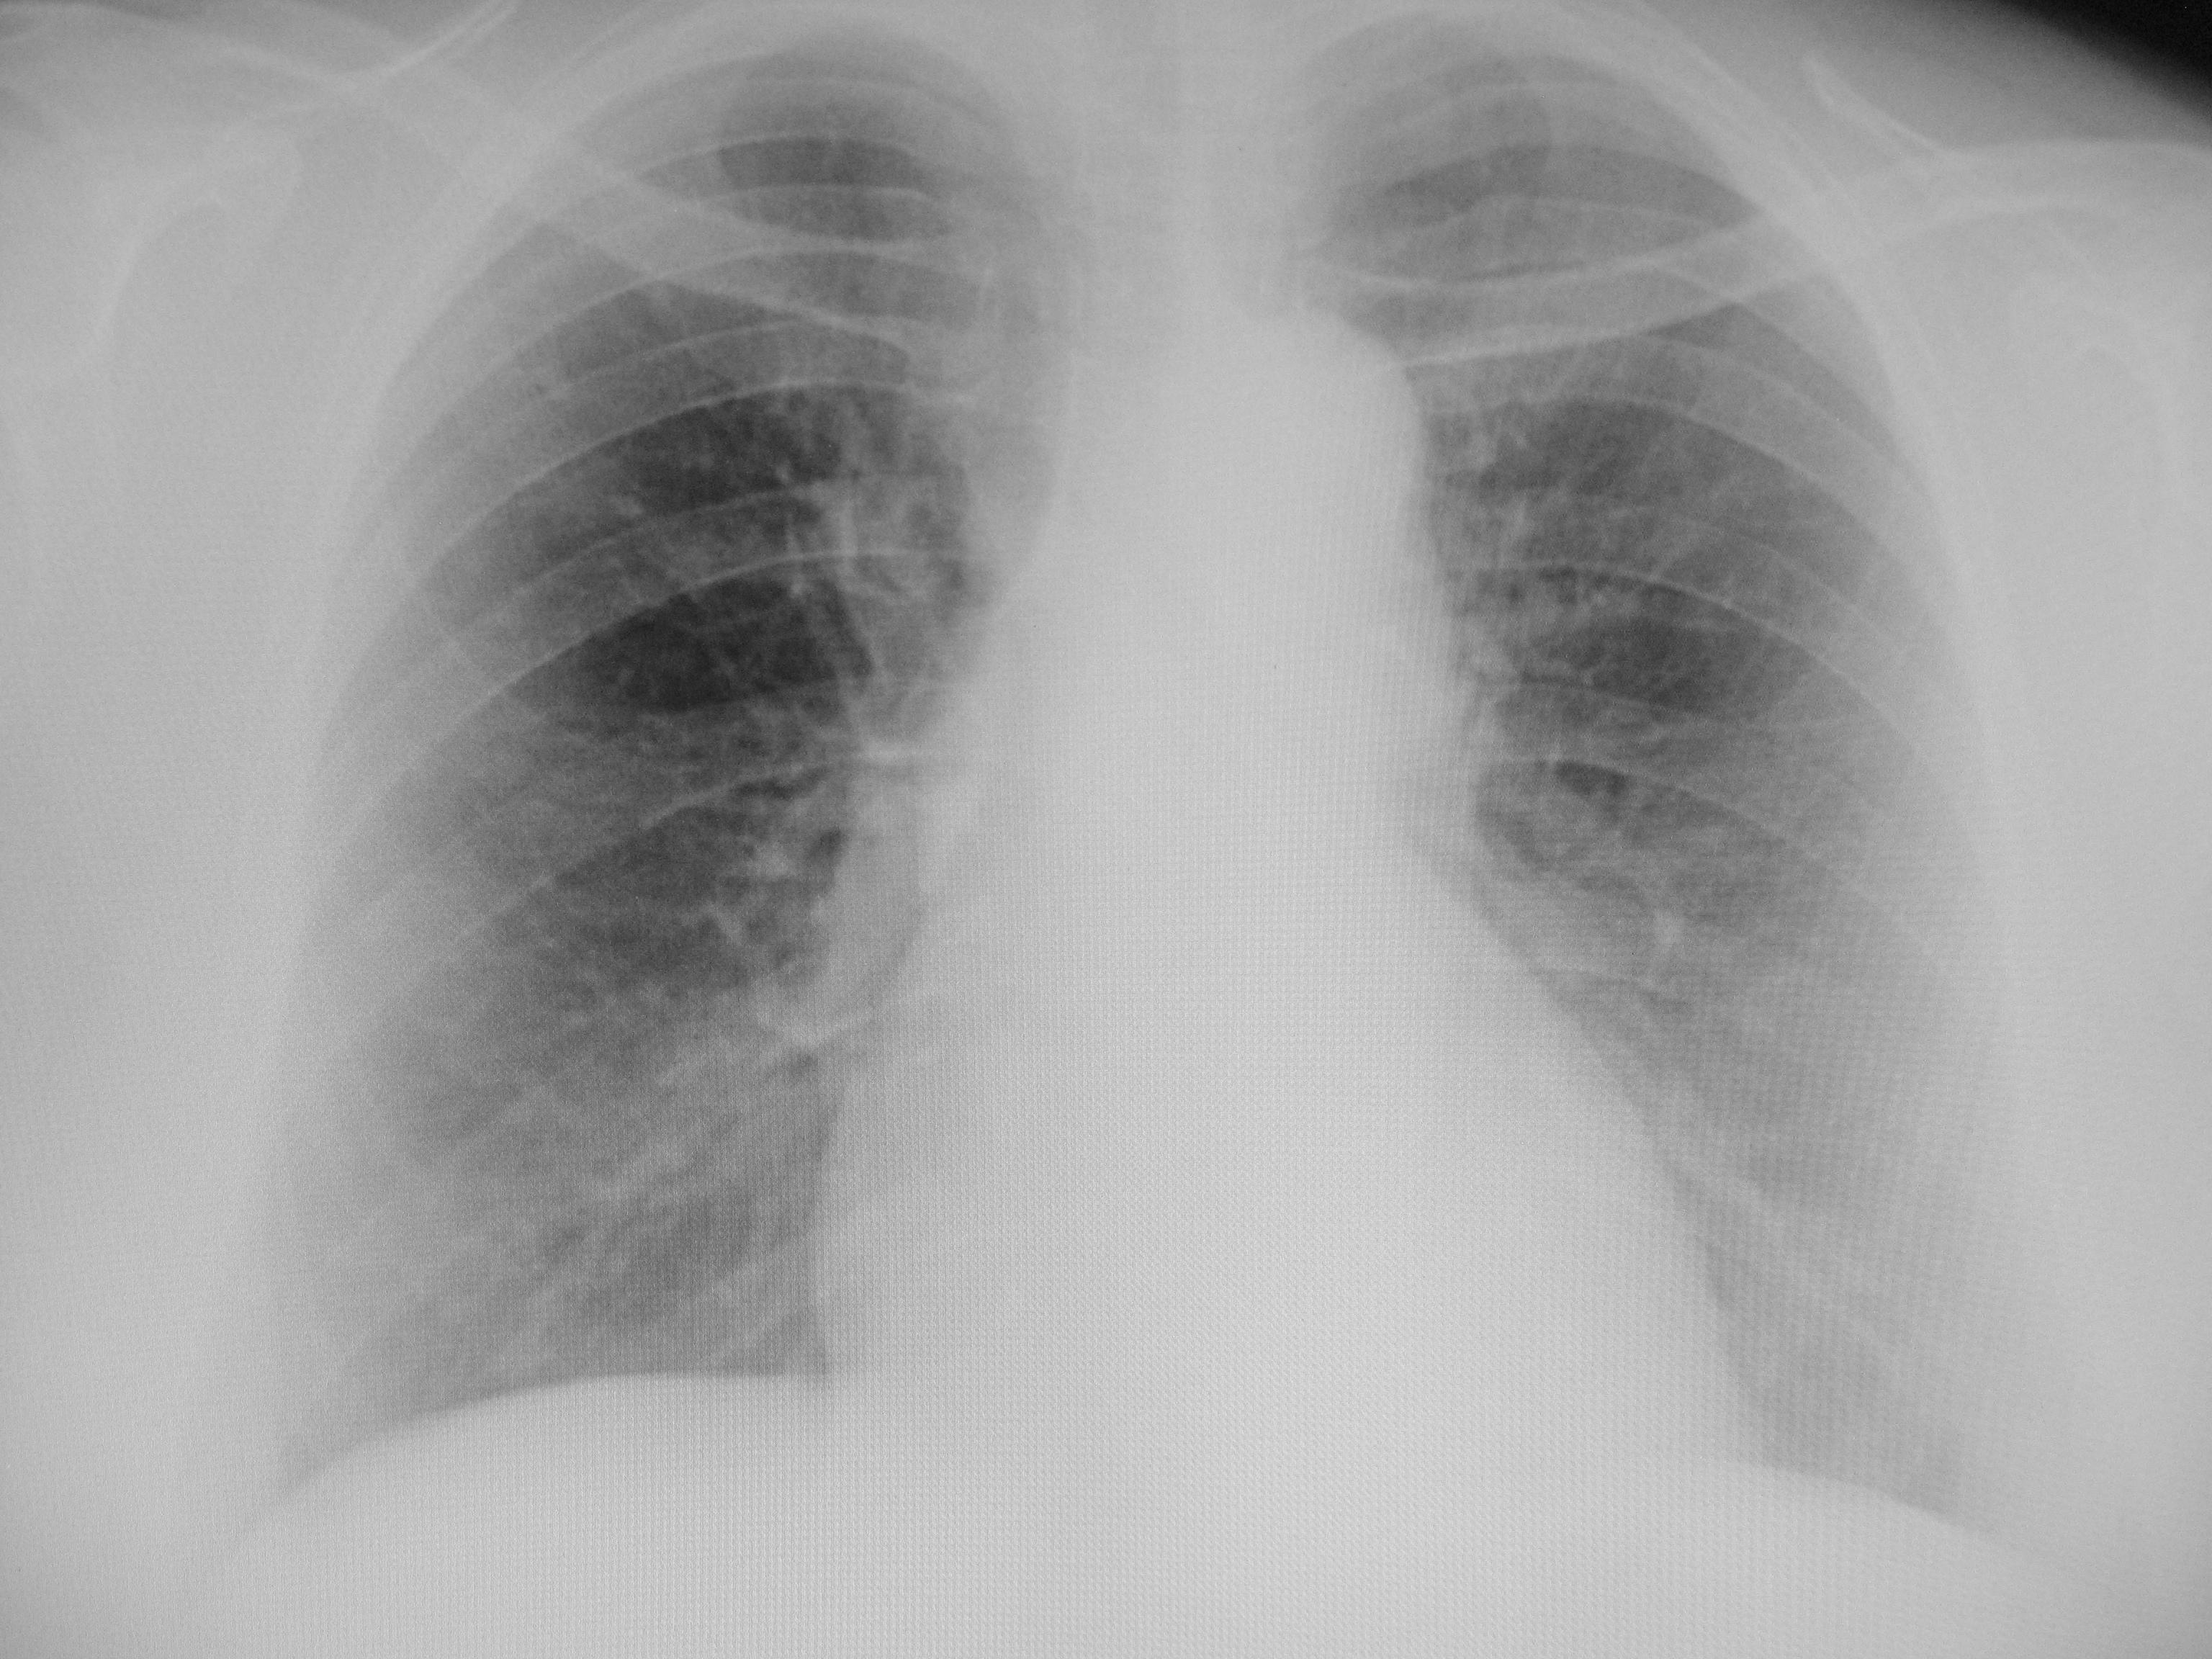

Пациент 1975 гр, страдает ревмат артритом, для ВТЭК, есть ли диффузный пневмосклероз?

№5 -Норма

№5 - есть сетчатость рисунка и усиление его, я бы написала диффузный пневмосклероз